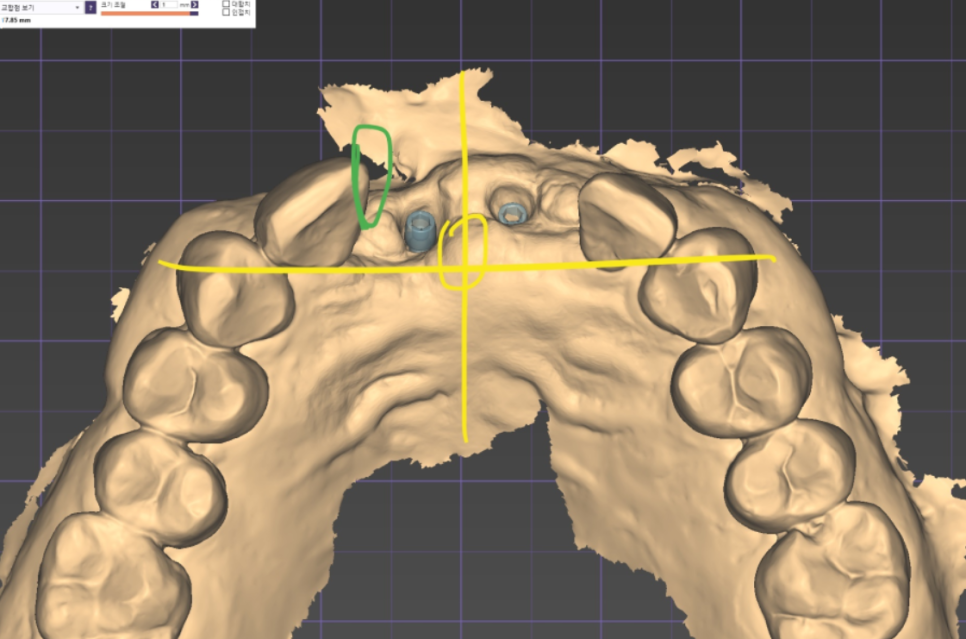

3D 구강 스캐너로 얻은 정밀한 데이터는

컴퓨터상에서 입체적인 모델로 구현됩니다.

사진 속에 보이는

파란색 기둥들은 스캔 바디라고 부르는데요,

잇몸 속에 심어진 임플란트가

어느 깊이와 각도로 자리 잡고 있는지

컴퓨터가 정확하게 인식할 수 있도록

도와주는 이정표 역할을 하죠.

이렇게 확보된 디지털 데이터를 바탕으로

환자분의 얼굴형과 주변 치아에

가장 잘 어울리는 모양을 정교하게 설계합니다.

사진 속 노란색 치아들이

바로 환자분의 새로운 앞니가 될 디자인이에요.

컴퓨터상에서 대칭과 비율을 0.1mm 단위까지

세밀하게 조정하기 때문에,